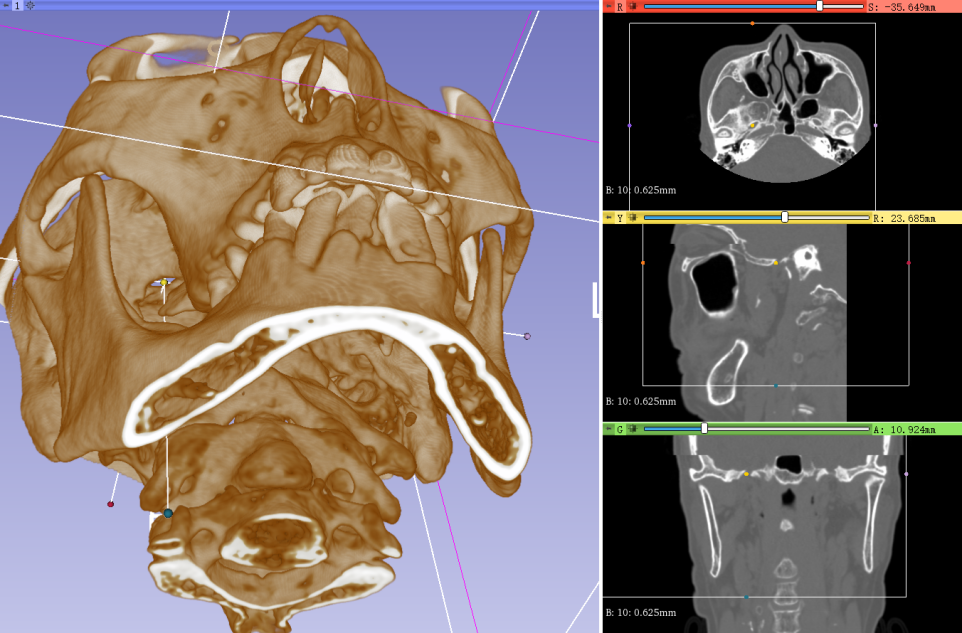

图1利用3Dslicer软件对DSA数据进行三维重建,精准评估卵圆孔及Meckel’s囊解剖结构

手术充分发挥复合手术室DSA设备的平台优势,将精准医疗理念贯穿全程。术前,依托DSA的高清三维重建技术,手术团队可从任意角度立体呈现颅底卵圆孔的细微解剖结构,精确测量其大小、形态与走向,并对穿刺路径反复模拟推演,确保每个角度安全无误。术中,依托双平面DSA的动态成像功能,采用“正位定向、侧位定深”的双轨验证策略——正位透视实时校准穿刺针与卵圆孔的对准方向,侧位影像精准把控进针深度,使穿刺针一次性精准抵达三叉神经半月结目标靶点。整个手术从麻醉到结束仅用时30分钟,患者术后即刻清醒,疼痛完全消失,肢体活动正常,真正实现了“针入痛止”的立竿见影之效。

图2、3:患者全麻后利用复合手术室DSA三维重建技术,穿刺针精准穿刺卵圆孔,进入Meckel's囊。

据郝铭主任医师介绍,该技术的核心在于精准与高效。DSA辅助三维重建将卵圆孔的定位从“凭经验估算”升级为“可视化导航”,有效避免反复穿刺对周围组织造成的损伤,不仅显著缩短手术时间,也大大提高了治疗的安全性与疗效。

三叉神经痛素有“天下第一痛”之称,其微创治疗的关键在于将穿刺针精准送达颅底的卵圆孔。传统治疗多在C臂机二维引导下进行,如同“盲人摸象”——仅能提供侧位影像,无法清晰显示卵圆孔的空间位置,医生往往需凭经验反复调整穿刺角度。这不仅延长了手术时间,也增加了患者反复穿刺的痛苦和风险。

而此次采用的DSA辅助三维重建技术,相当于为穿刺针装上了“立体导航系统”。术前通过三维成像清晰勾勒卵圆孔的大小、形态和走行,规划出最佳穿刺路径;术中借助双平面DSA的“正位定向、侧位定深”功能,实现从“凭经验估算”到“可视化导航”的跨越,确保穿刺针一次成功、精准到位,最大程度减少了周围组织损伤。